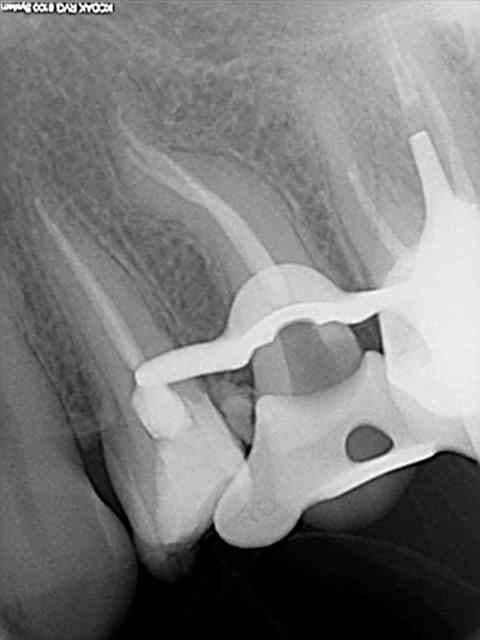

Tiens en parlant d'honneur la je meriterais un grand doigt.

Protaper dans la racine mesiale, amlg dans la racine distale, Mais j'ai mis la digue :p.

Conclusion RAS au controle a 1 an !

Comme dit Stéphane tous les moyens sont bons tant qu on arrive au résultat escompté ;p